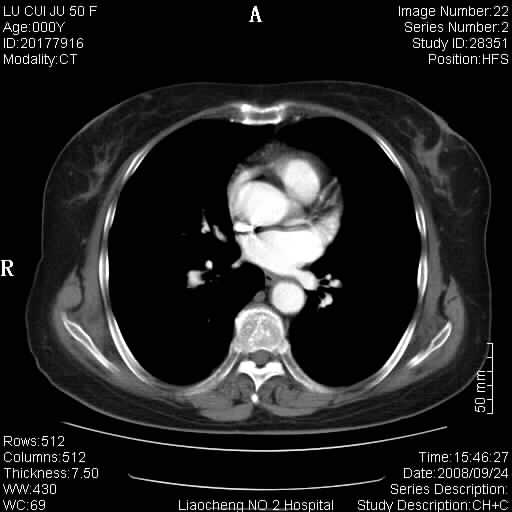

标题: CT15870:F50Y,纵膈占位,是不是胸腺瘤,请各位高手讨论。

临床表现为重症肌无力;ct增强扫描可见前纵膈胸腺部位弥漫性簇状软组织节结灶,不知道是不是胸腺瘤,请各位高手讨论。

胸腺外缘稍向外突,未见确切占位改变。结合临床考虑胸腺增生可能性大。

考虑胸腺增生

考虑胸腺增生!!